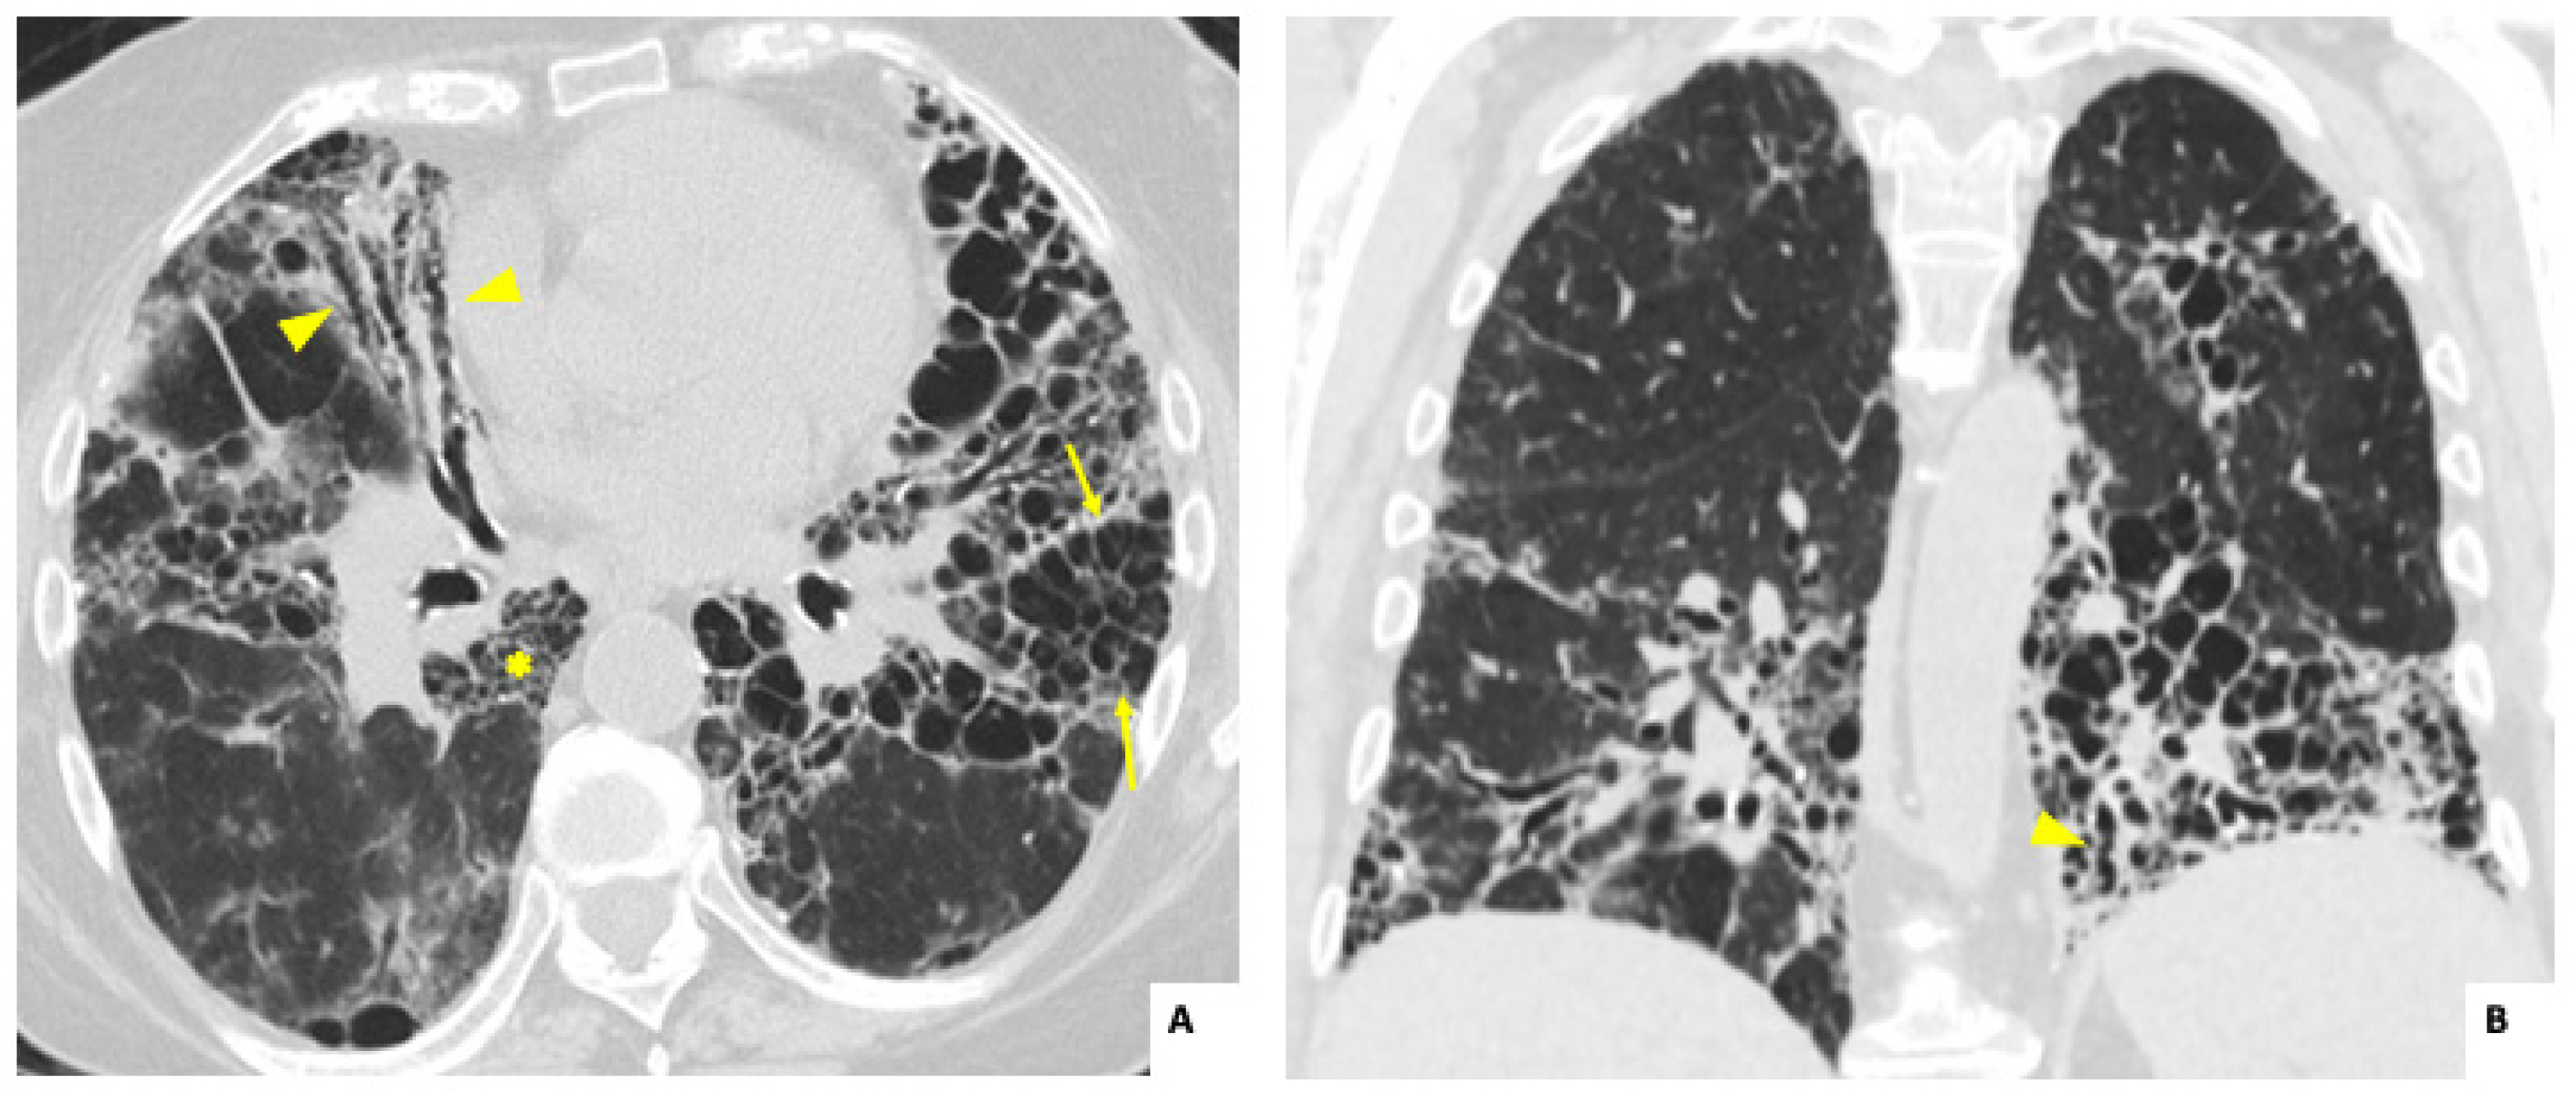

3.2. Radiological and Lung Function Findings

| Radiological features in HRCT | ||||

| Nodules, n (%) | 2 (8.7) | 2 (15.3) | 0 (0) | 0.092 |

| Lung consolidation, n (%) | 8 (34.8) | 2 (15.3) | 6 (60) | 0.039 |

| Ground glass opacities, n (%) | 17 (73.9) | 9 (69.2) | 8 (80) | 0.66 |

| Traction bronchiectasis, n (%) | 19 (82.6) | 13 (100) | 6 (60) | 0.024 |

| Reticulation, n (%) | 15 (65.2) | 10 (76.9) | 5 (50) | 0.179 |

| Honeycomb, n (%) | 8 (34.8) | 5 (38.4) | 3 (30) | 0.673 |

| Radiological pattern in HRCT | ||||

| UIP, n (%) | 12 (52.2) | 9 (69.2) | 3 (30) | 0.161 |

| NSIP, n (%) | 6 (26) | 1 (7.7) | 5 (50) | 0.022 |

| Fibrotic NSIP, n (%) | 5 (21.7) | 4 (30.7) | 1 (10) | 0.09 |

| OP, n (%) | 5 (21.7) | 3 (23) | 2 (20) | 0.673 |